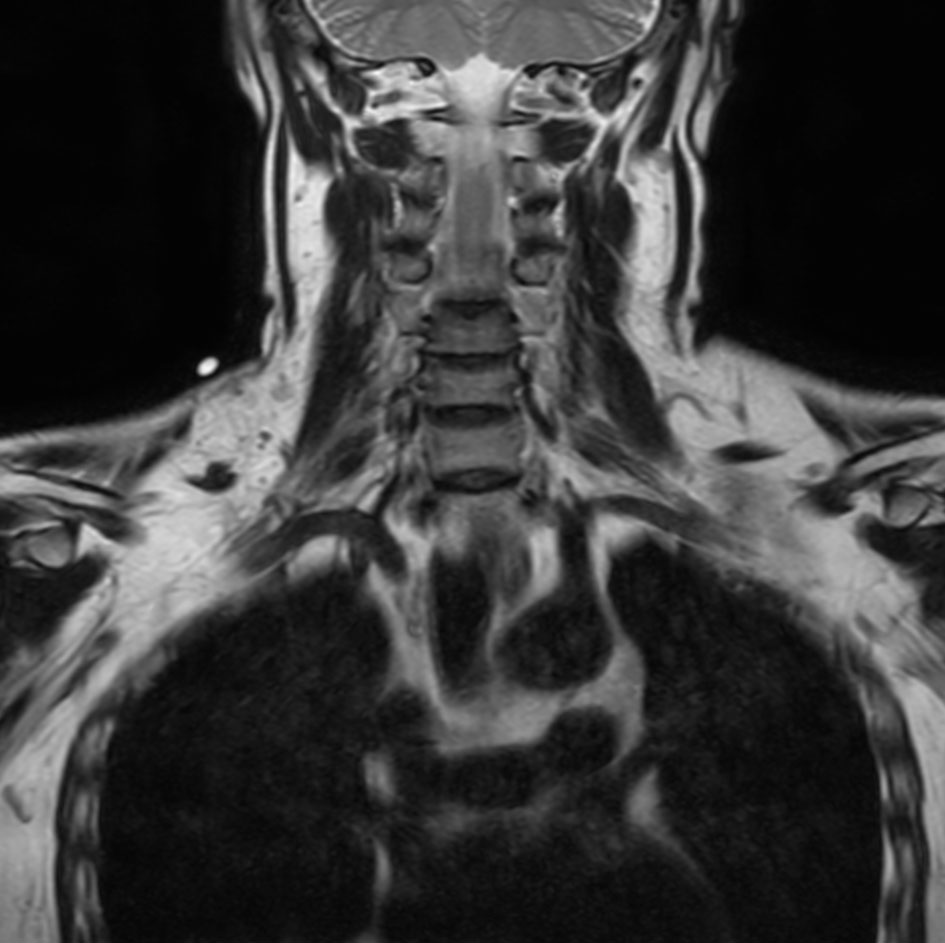

Coronal T2w mDIXON XD TSE (In Phase)

Coronal T2w mDIXON XD TSE (Water only)

Coronal T2w VISTA